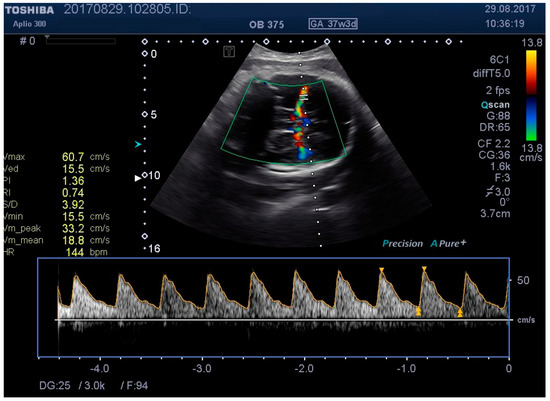

Figure 5. MCA Doppler spectrum with baseline pressure.